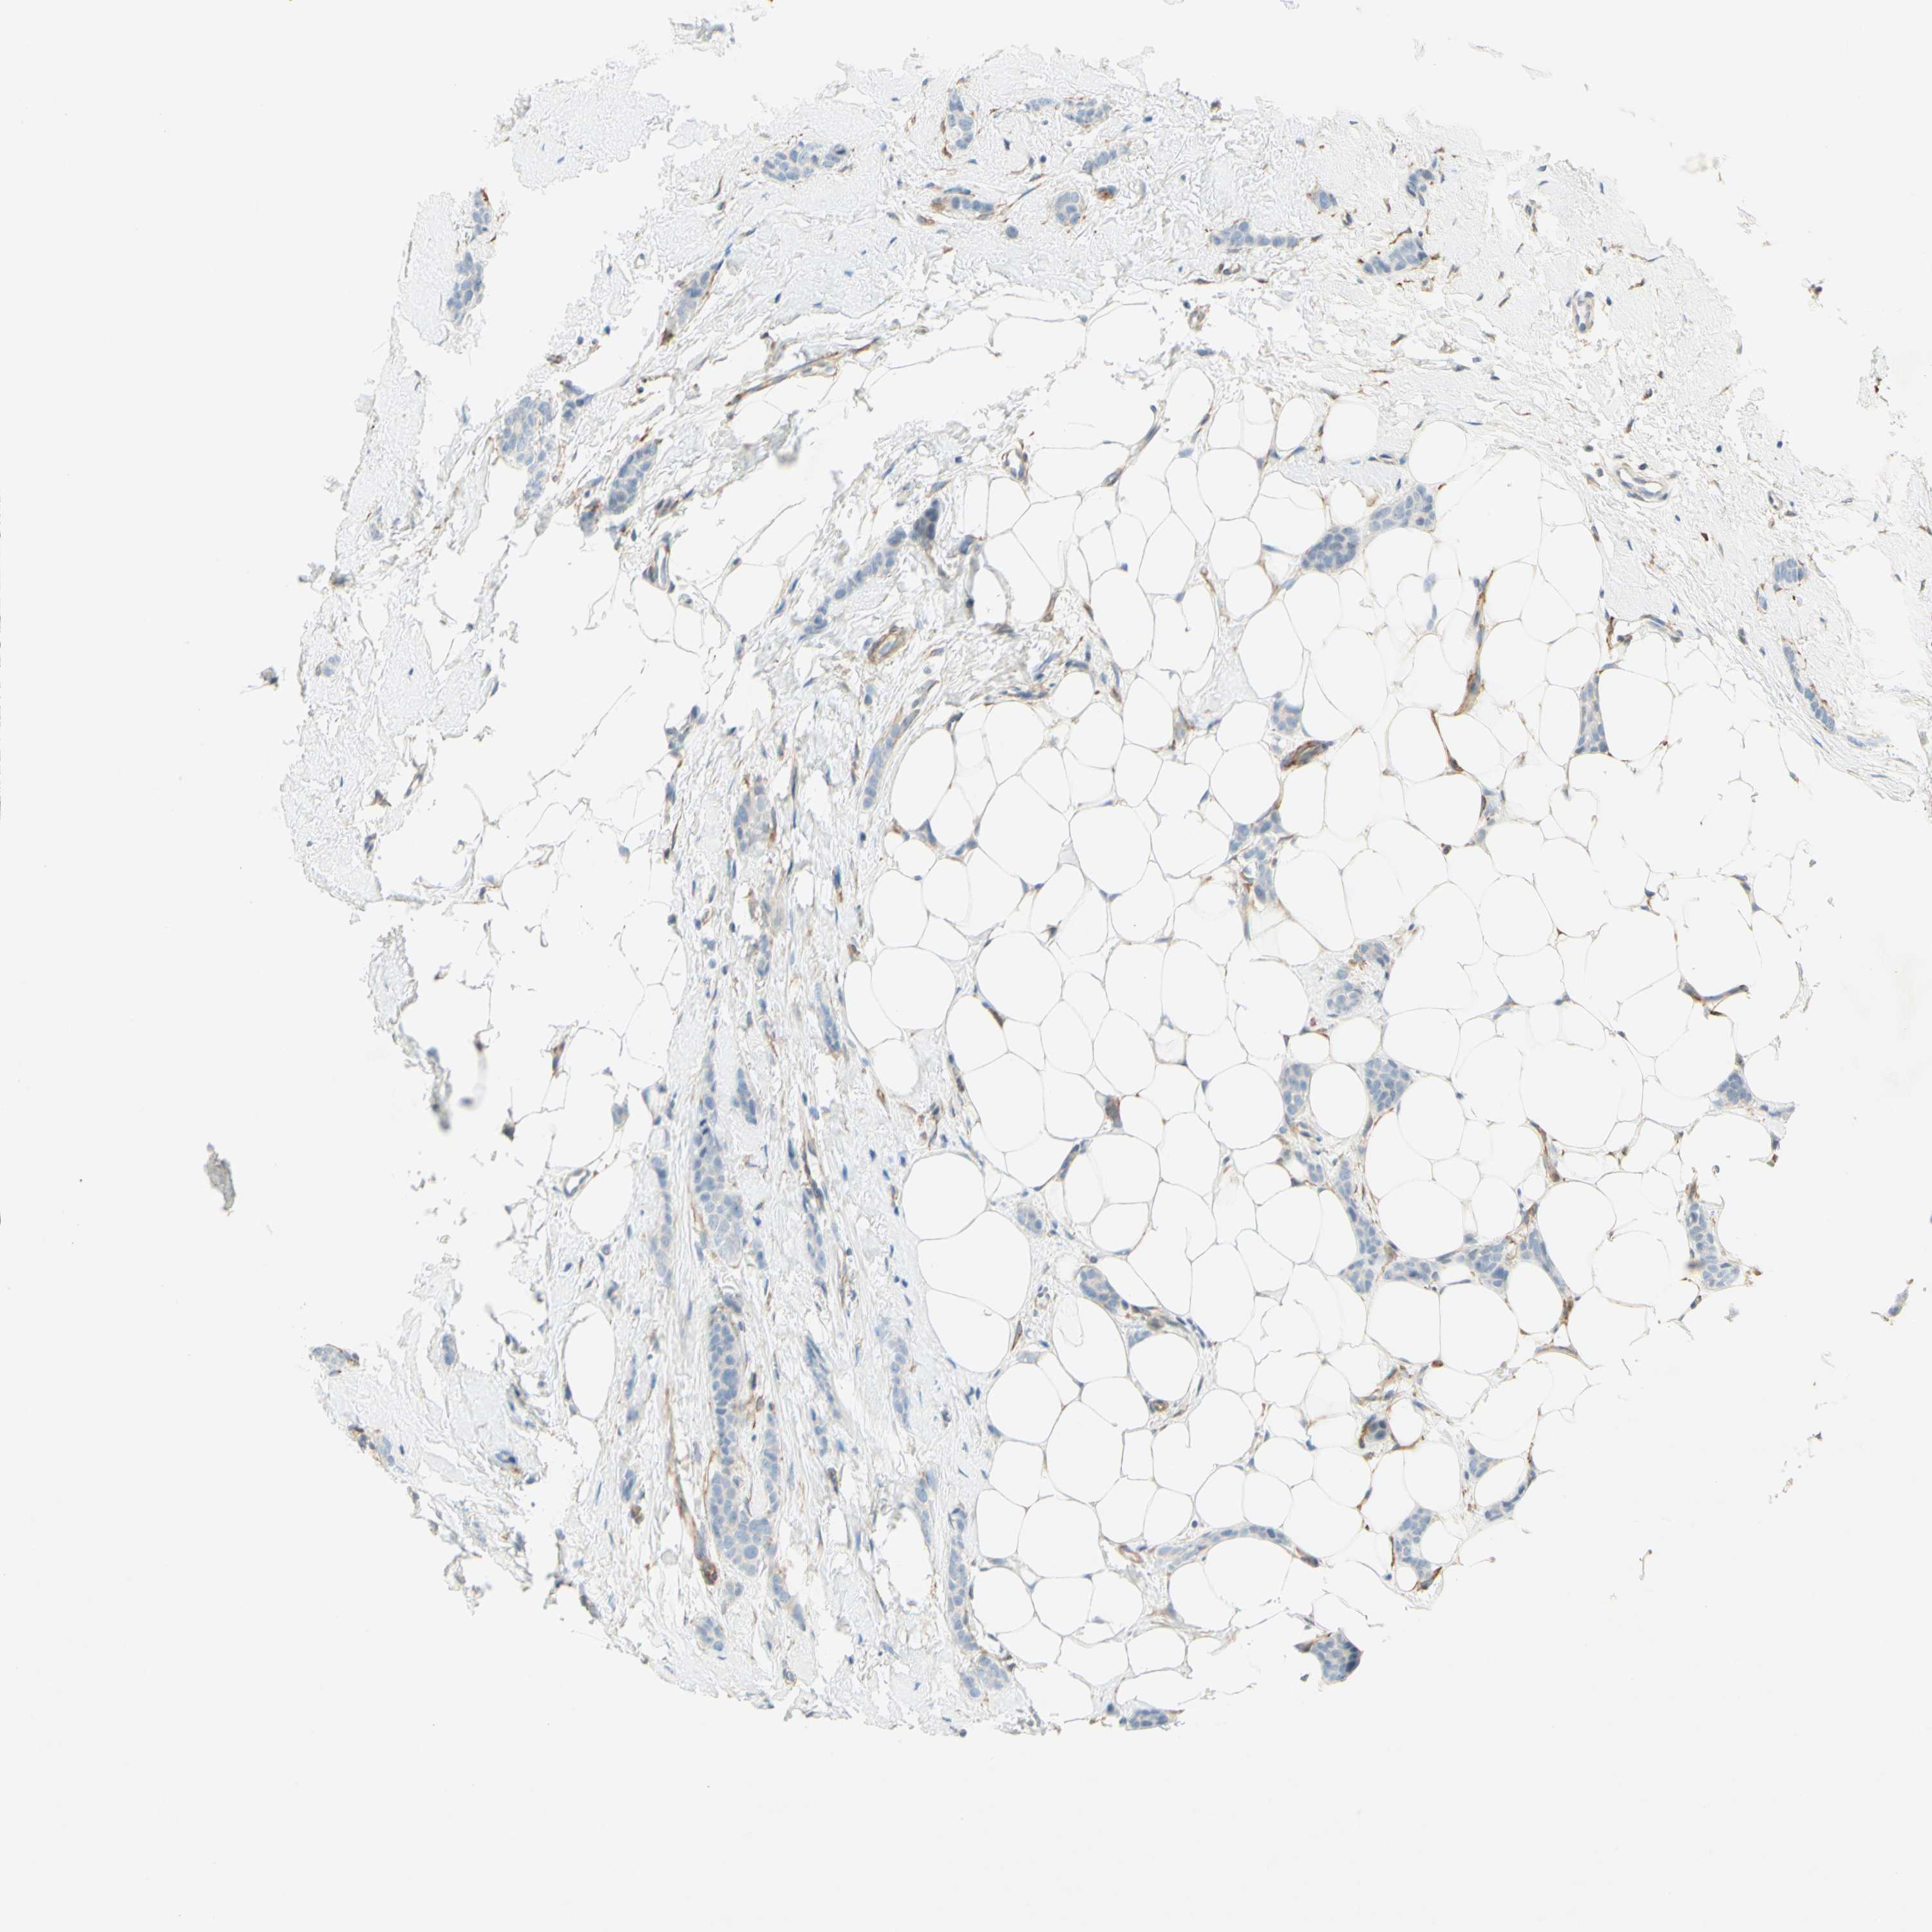

CANCER BREAST CANCER Show tissue menu

BRCA TCGA BRCA VALIDATION PROTEIN EXPRESSION

ANTIBODIES

AND

VALIDATION